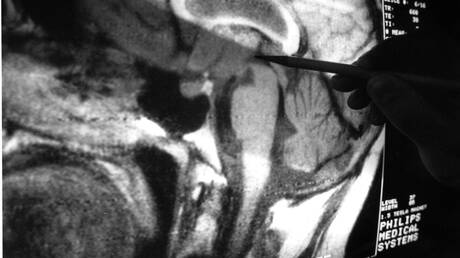

Η επαναστατική περίπτωση του ανθρώπου με «δύο εγκεφάλους» – Ή πώς μια έρευνα άλλαξε τη νευροεπιστήμη

Μάικλ Σ. Γκαζανίγκα: Ένας από τους σπουδαιότερους νευροεπιστήμονες του 20ου αιώνα που έδωσε στην ανθρωπότητα μία άλλη…